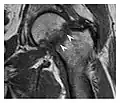

The greater tuberosity of the humerus is also an illustrative location of occult fractures. The osseous injury may follow seizures, glenohumeral dislocation, forced abduction, or direct impaction. They are commonly discovered on MRI in symptomatic patients with suspicion of rotator cuff tear. Coronal images are best suited for detection. They appear as crescentic oblique lines surrounded by a bone marrow edema pattern (Figure 5). The rotator cuff must be inspected since associated ligamentous lesions are common. In the ankle, malleoli and tarsal bones should be checked carefully for any cortical disruptions and radiolucent lines that may reveal a fracture. Awareness of the exact location of the pain will help direct the attention of the interpreter when searching for very subtle signs of fracture (Figure 6).[1]

Figure 6: Subtle anterior talar fracture in a 39-year-old man presenting with ankle pain after a fall. (a) Anteroposterior radiograph shows a subtle oblique radiolucent line through the talus (white arrows). (b) Sagittal CT reformation confirms the presence of an anterior talar fracture with cortical offset (black arrow). Avulsion fractures, which consist of a detached bone fragment resulting from a ligament or tendon pulling away from the bone, may also present with subtle radiographic signs. Tiny osseous fragments near the presumed attachment site of a ligament suggest this diagnosis. Common sites are the lateral tibial plateau (the Segond fracture), the spinal tuberosity of the tibia resulting from anterior cruciate ligament avulsion, and the ischial tuberosity.[1]